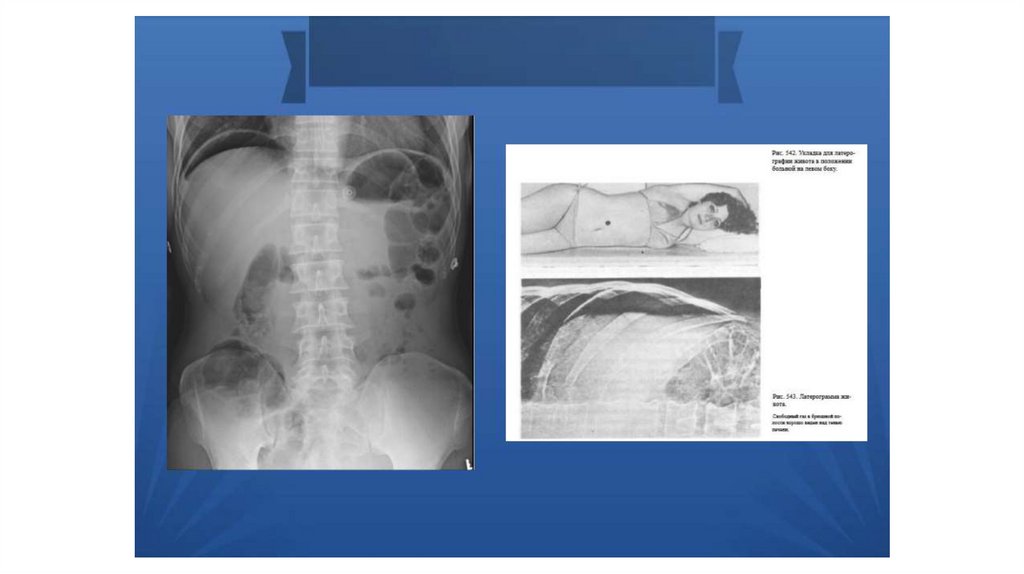

Прободная язва

Прободная язва желудка

Прободные гастродуоденальные язвы